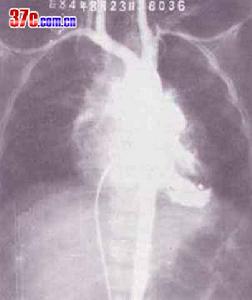

心臟X光片主動脈:四聯症病例主動脈位置向前向右移位,起源於兩側心室,騎跨於右心室的部分一般占主動脈口徑的50%,主動脈根部比正常增大並呈順鐘向轉位,致使無冠瓣基部向右向上移向心室間隔的後上緣。右心室流出道瀰漫性發育不良,漏斗部間隔小,肺動脈開口向左移位者主動脈右位及騎跨更為明顯。約25%的病例呈現右位主動脈弓,10%的病例有迷走左鎖骨下動脈直接起源於降主動脈。肺動脈閉鎖的病人常伴有動肺導管未閉。

選擇性右心室造影檢查:法樂四聯症病例決定手術治療之前必需作選擇性右心室造影術。於右心室腔內放入心導管注射造影劑,連續X線拍片檢查可顯示肺動脈和主動脈同時顯影和主動脈騎跨程度,與此同時造影劑從右心室經心室間隔缺損進入左心室。造影檢查尚能顯示右心室流出道及/或肺動脈狹窄的部位和程度,了解肺動脈發育情況和測量肺動脈總乾和升主動脈的直徑,計算兩者的比值。

逆行主動脈造影檢查:可顯示動脈導管未閉,支氣管動脈側支循環發育情況和主動脈瓣啟閉功能。McGoon測量左、右肺動脈和膈肌平面降主動脈直徑,如左、右肺動脈直徑之和與降主動脈直徑之比大於2.0,則說明肺動脈血流無梗阻。